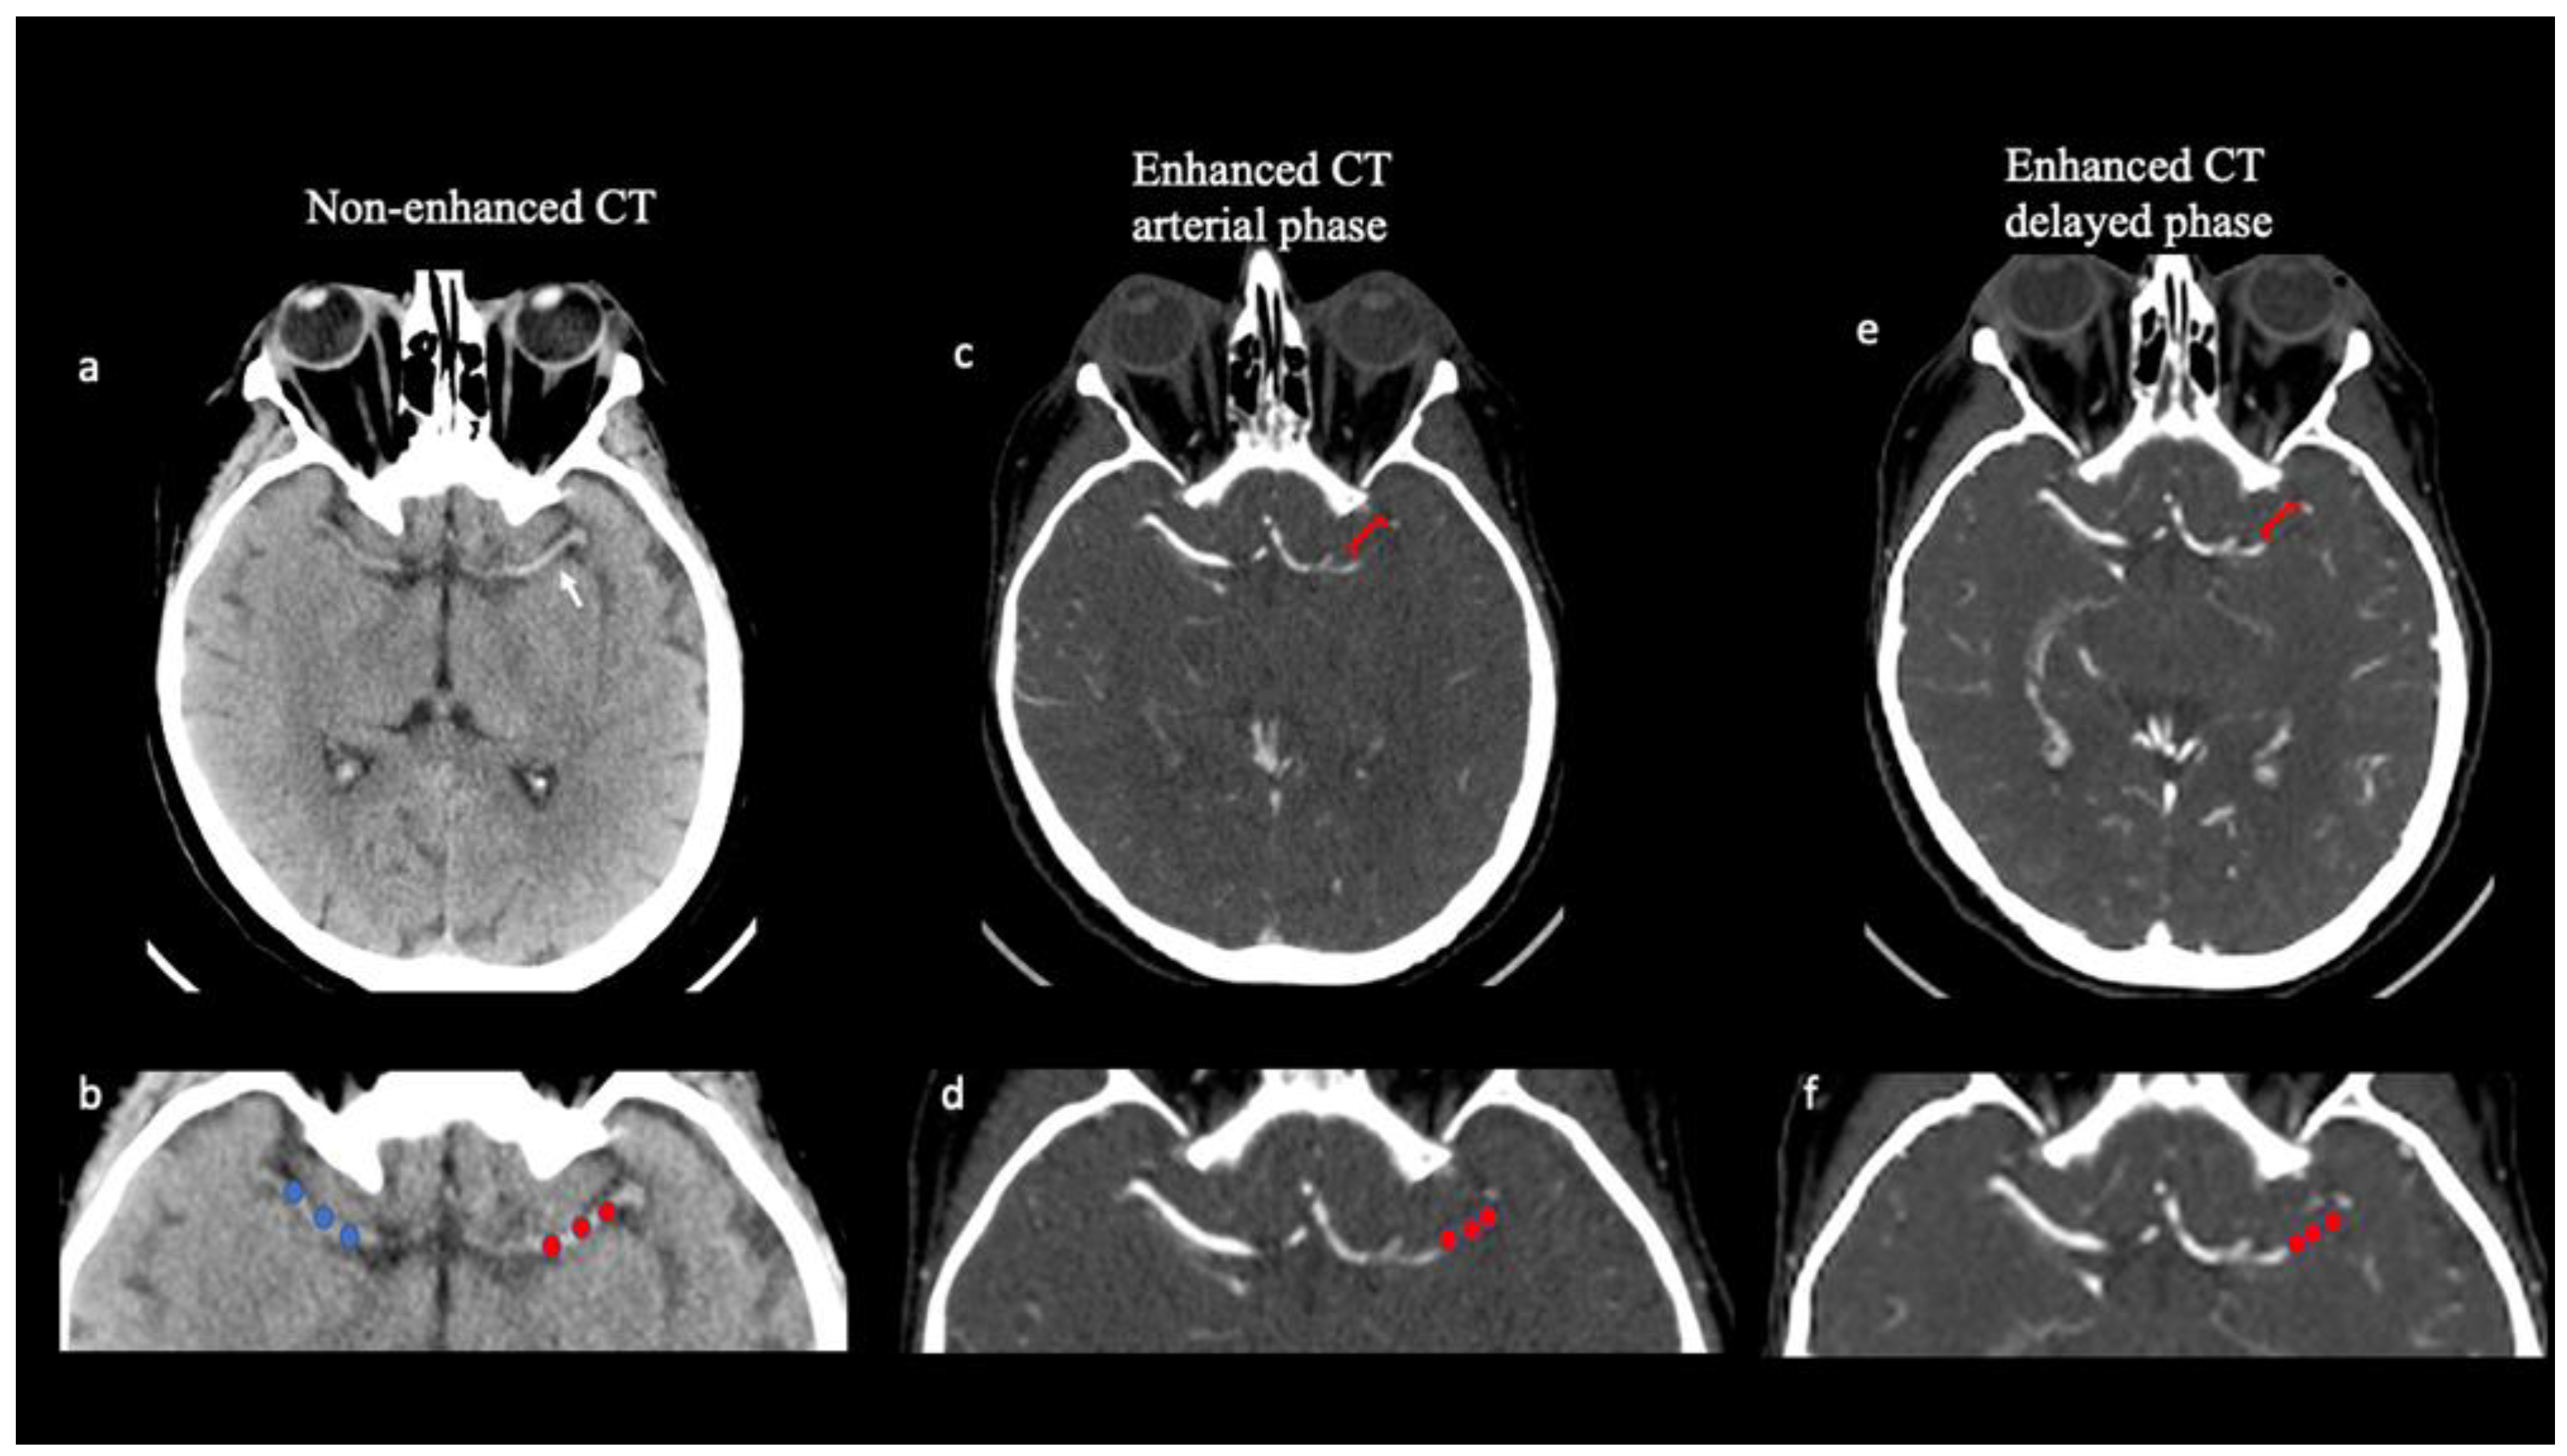

On NCCT imaging, the thrombus HU value was calculated by placing three spherical regions of interest (ROIs) within the thrombus location (size 3 × 3 voxels) (proximal, middle, and distal clot segment) but away from the boundaries of the thrombus (Figure 1). HU values were also calculated, using ROIs placed in three corresponding locations, on the contralateral artery to correct for the variability of hematocrit levels. The mean thrombus attenuation on NCCT was calculated by averaging the HU of the three ROIs both in the thrombosed and the contralateral arteries. On NCCT, thrombus average attenuation measurement (dHU) was calculated as the difference between the thrombus HU average value (tHU) and the HU average value on the contralateral side (cHU).

Thrombus attenuation measurements and thrombus perviousness quantification. Axial non-contrast CT (NCCT; a,b) demonstrates a hyperattenuating (“dense”) middle cerebral artery (MCA) (white arrow in a) in a 67-year-old patient with acute stroke. Thrombus attenuation measurement was calculated on NCCT as the difference between thrombus average density and contralateral artery by placing 3 spherical ROIs in the proximal, middle, and distal parts of the thrombus in the M1 segment of the left middle cerebral artery (red ROIs in b) and along the same vessel on the contralateral side (blue ROIs in b). Multiphase CTA (mCTA; c–f) identifies occlusion length of the M1 segment of the left middle cerebral artery, demonstrated as contrast-filling defects (square bracket in c,e). Three regions of interest (red ROIs) were placed in a left middle cerebral artery thrombus both in the arterial (c,d) and in the delayed phases (e,f) of the mCTA. Clot perviousness measurement was calculated as the difference in average thrombus attenuation measured on the arterial or delayed phase of mCTA and on NCCT.

The occlusion extension, defined as clot length, was determined based on the contrast-filling defects between the proximal and distal thrombus borders found on the delayed phase of CTA. Delayed phase images were chosen because they allowed the maximum amount of time to allow a contrast to reach the distal face of the clot from leptomeningeal collaterals. Mural calcifications were excluded from the analysis (Figure 1).

Thrombus HU average value was calculated both on NCCT and mCTA imaging. The clot perviousness measures the contrast penetration into a thrombus [20]. To estimate contrast penetration into the thrombus, the increase in the mean HU of the thrombus on mCTA was compared with the mean HU of the clot on NCCT. In the mCTA, two measurements of the average thrombus density were performed in the arterial and delayed phases, respectively, using the same method. Thrombus attenuation was measured both for the arterial (Perviousness pre-post 1) and delayed (Perviousness pre-post 2) phase of the mCTA (Figure 1).